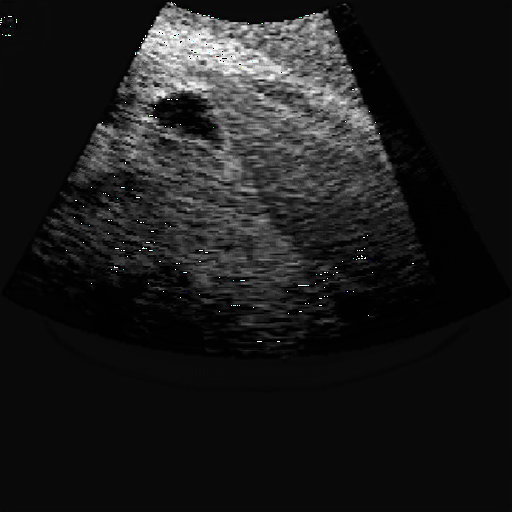

Fig. 5 and 6 present examples of the translation results from CT to ultrasound. These visual comparisons demonstrate that the S-CycleGAN can not only mimic the ultrasound style but also preserve critical anatomical features compared with Fig. 3. The synthetic images closely resemble real ultrasound scans in terms of texture and shape, suggesting a high level of detail preservation.

Refer to caption

(a) Real CT

(b) Fake US

(c) CT Label

(d) Predicted US Mask

Figure 6: CT-to-ultrasound translation example.2